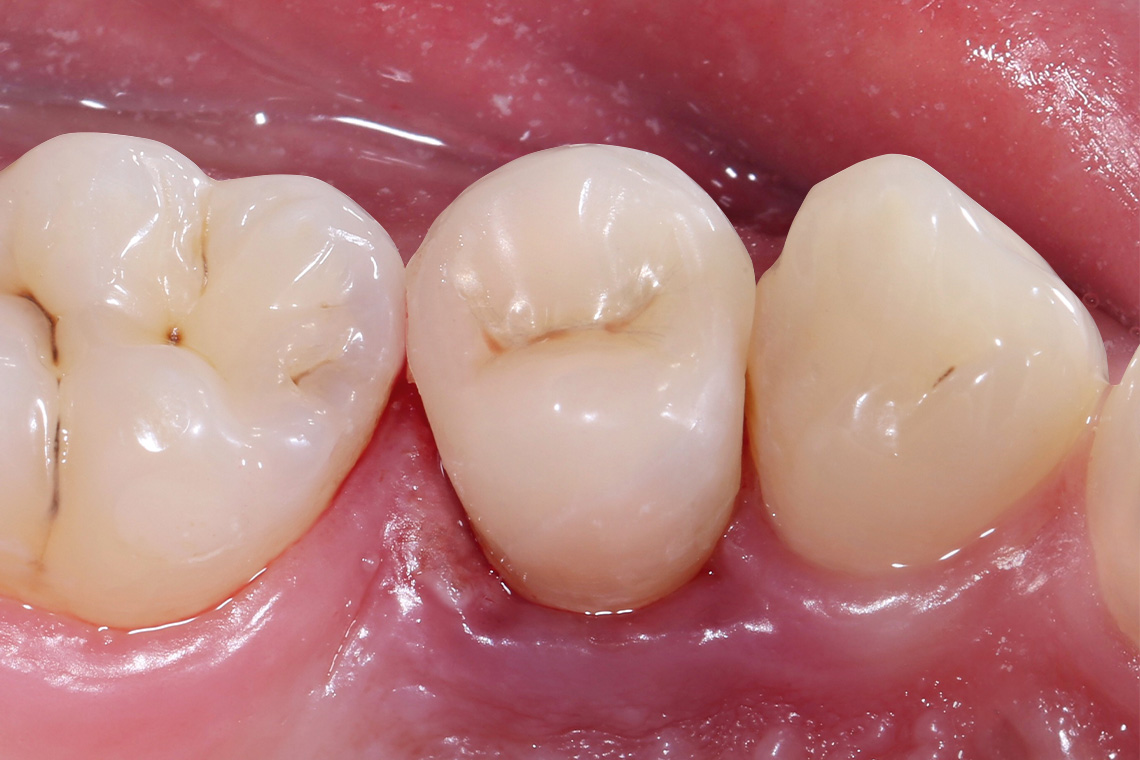

VITA ENAMIC multiColor Endokrone: Ausgangssituation vs. Finales Ergebnis

Ergebnis: VITA ENAMIC multiColor integrierte sich harmonisch in die natürliche Zahnsubstanz. Die insuffiziente Kompositfüllung an Zahn 14 (od) hatte zu Entzündungen im Zahnzwischenraum geführt.